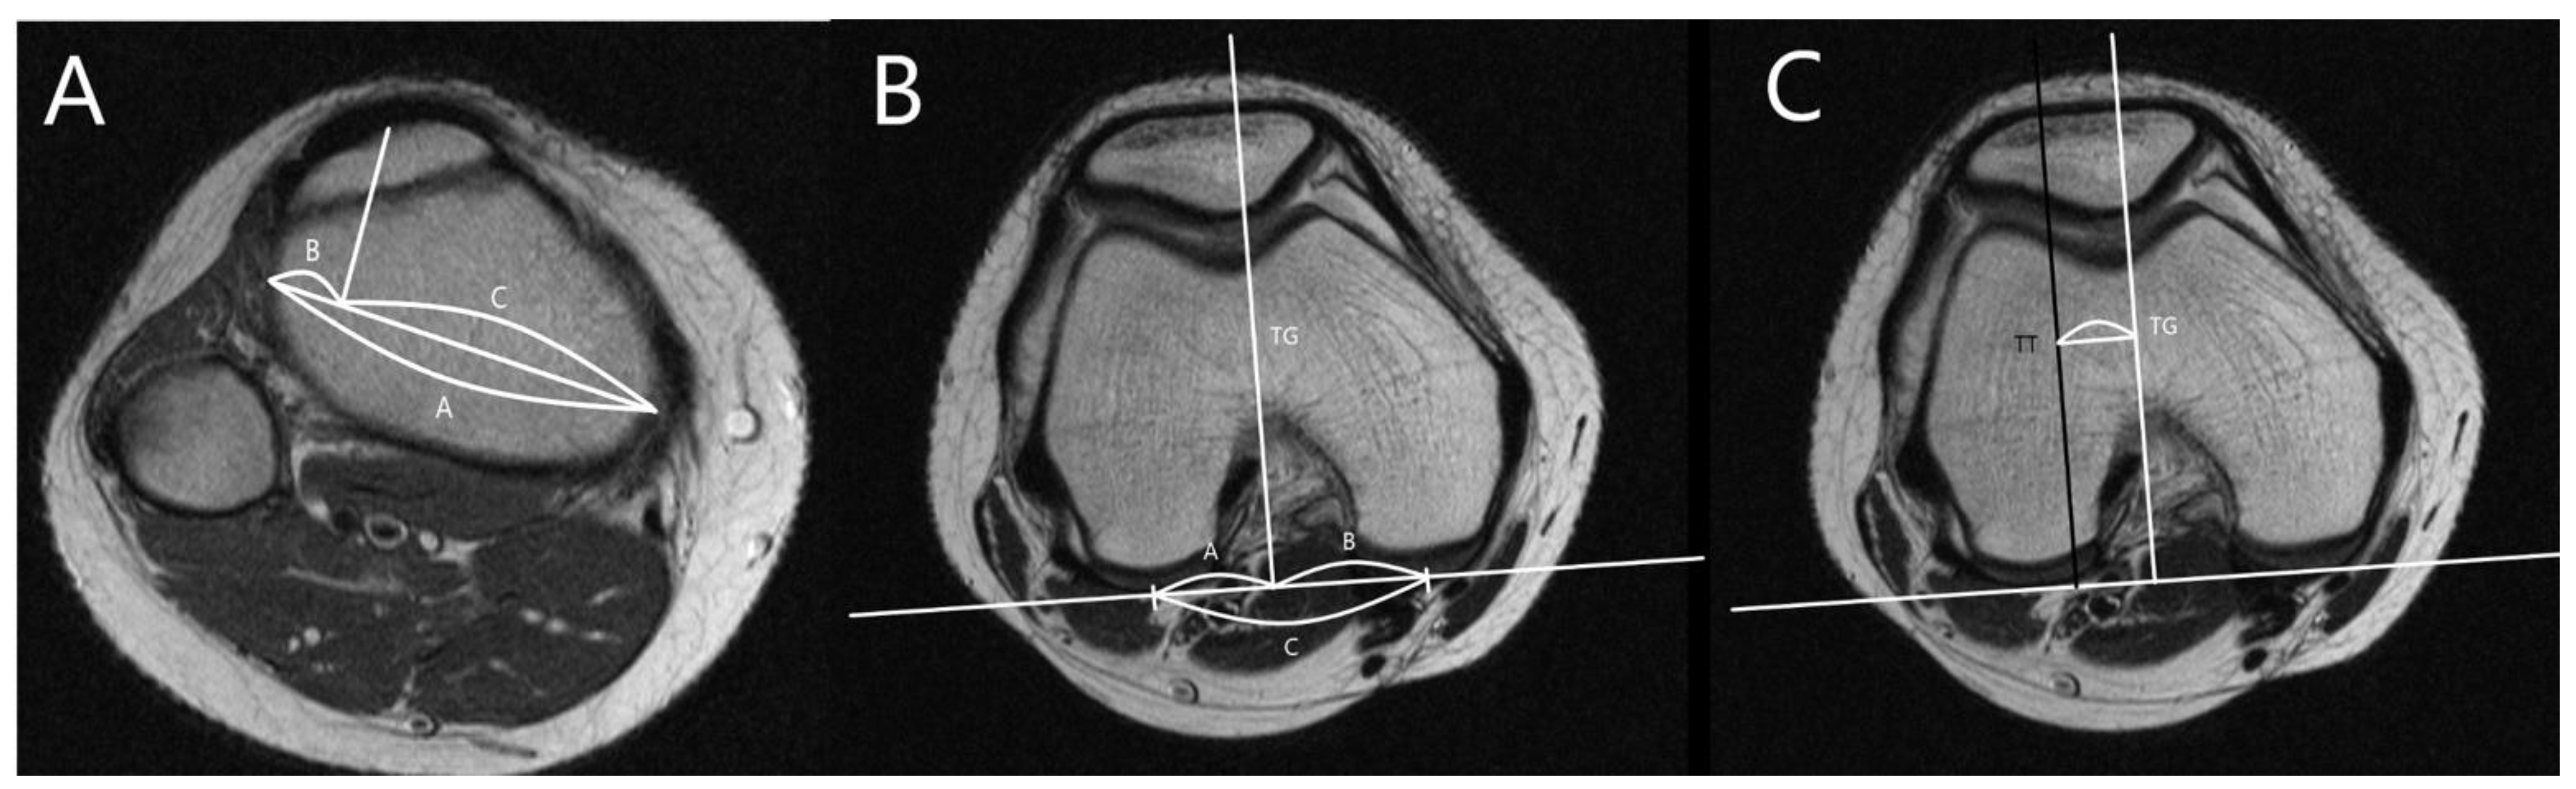

The MRI was performed using a 1.5T (GE Healthcare, Milwaukee, WI, USA). The slice thickness was 3 mm in all sequences. The T1 fat saturation axial imaging was utilized to measure all parameters. The cartilaginous parameters of the patellofemoral morphology including sulcus angle (SA), lateral trochlear inclination (LTI), trochlear facet asymmetry (TFA), and femoral depth (FD) and alignment as well as tibial tuberosity–trochlear groove distance (TT-TG), percent sulcus location (PSL), and percent tibial tuberosity location (PTL) were assessed. Three orthopedic surgeons measured all parameters twice at 8-week intervals using image archiving and communication systems (Maroview, Marotech, Seoul, Korea). The morphological parameters of the patellofemoral joint were measured in the axial slice of MRI, which showed the deepest trochlear groove [18]. SA was defined as the angle between slopes of the medial and lateral trochlea [21,22]. LTI was measured as the angle between a line along with cartilage of lateral trochlear facet and the line along the posterior aspect of the femoral condyle (posterior condylar axis) [21]. TFA was defined as the ratio of the length of the medial trochlear facet to that of the lateral trochlear facet [21,23]. FD was defined as the distance between the deepest point of the trochlear sulcus and posterior condylar axis subtracted from the mean anteroposterior length of medial and lateral femoral condyles (Figure 2) [24].

Figure 2.

Measurements for trochlear morphology. (A) Measurement of sulcus angle (SA), the angle between slopes of the medial and lateral trochlea. (B) Measurement of lateral trochlear inclination (LTI), the angle between a line along with cartilage of lateral trochlear facet and a line along with posterior aspects of femoral condyles (posterior condylar axis). (C) Measurement of trochlear facet symmetry (TFS), the ratio of the length of medial trochlear facet (line B) to that of lateral trochlear facet (line A) [B/A]. (D) Measurement of femoral depth (FD), distance C between the deepest point of the trochlear sulcus and posterior condylar axis subtracted from a mean anteroposterior distance of medial and lateral femoral condyles (lines B and D) [B + D/2 − C].

The alignment parameters of the patellofemoral joint were measured in the axial slice of the deepest trochlear groove and the most prominent tibial tuberosity [25]. The PTL, PSL, and TT-TG were measured as shown in Figure 3 [26,27].

Figure 3.

Position of the trochlear groove and tibial tuberosity. (A) Measurement of percent tibial tuberosity location (PTL). Lines B and C are divided by perpendicular lines from tibial tuberosity to line A [B/A × 100]. (B) Measurement of percent sulcus location (PSL). Lines E and F are divided by perpendicular lines from the deepest portion of the trochlear groove to a line along with posterior aspects of femoral condyles [E/D × 100]. (C) Measurement of tibial tuberosity—trochlear groove (TT-TG) distance, the distance from the deepest point of the trochlear groove to the tibial tuberosity.